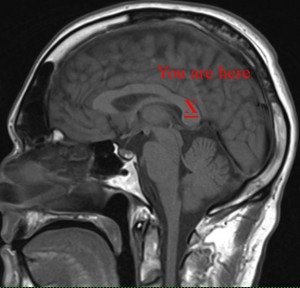

The MRI procedure was easy, and the images will give the ENT doctor the vision he needs inside my head. This method is much preferred to having him drill a ½” hole and root around my brain with a screwdriver or however they do that stuff.